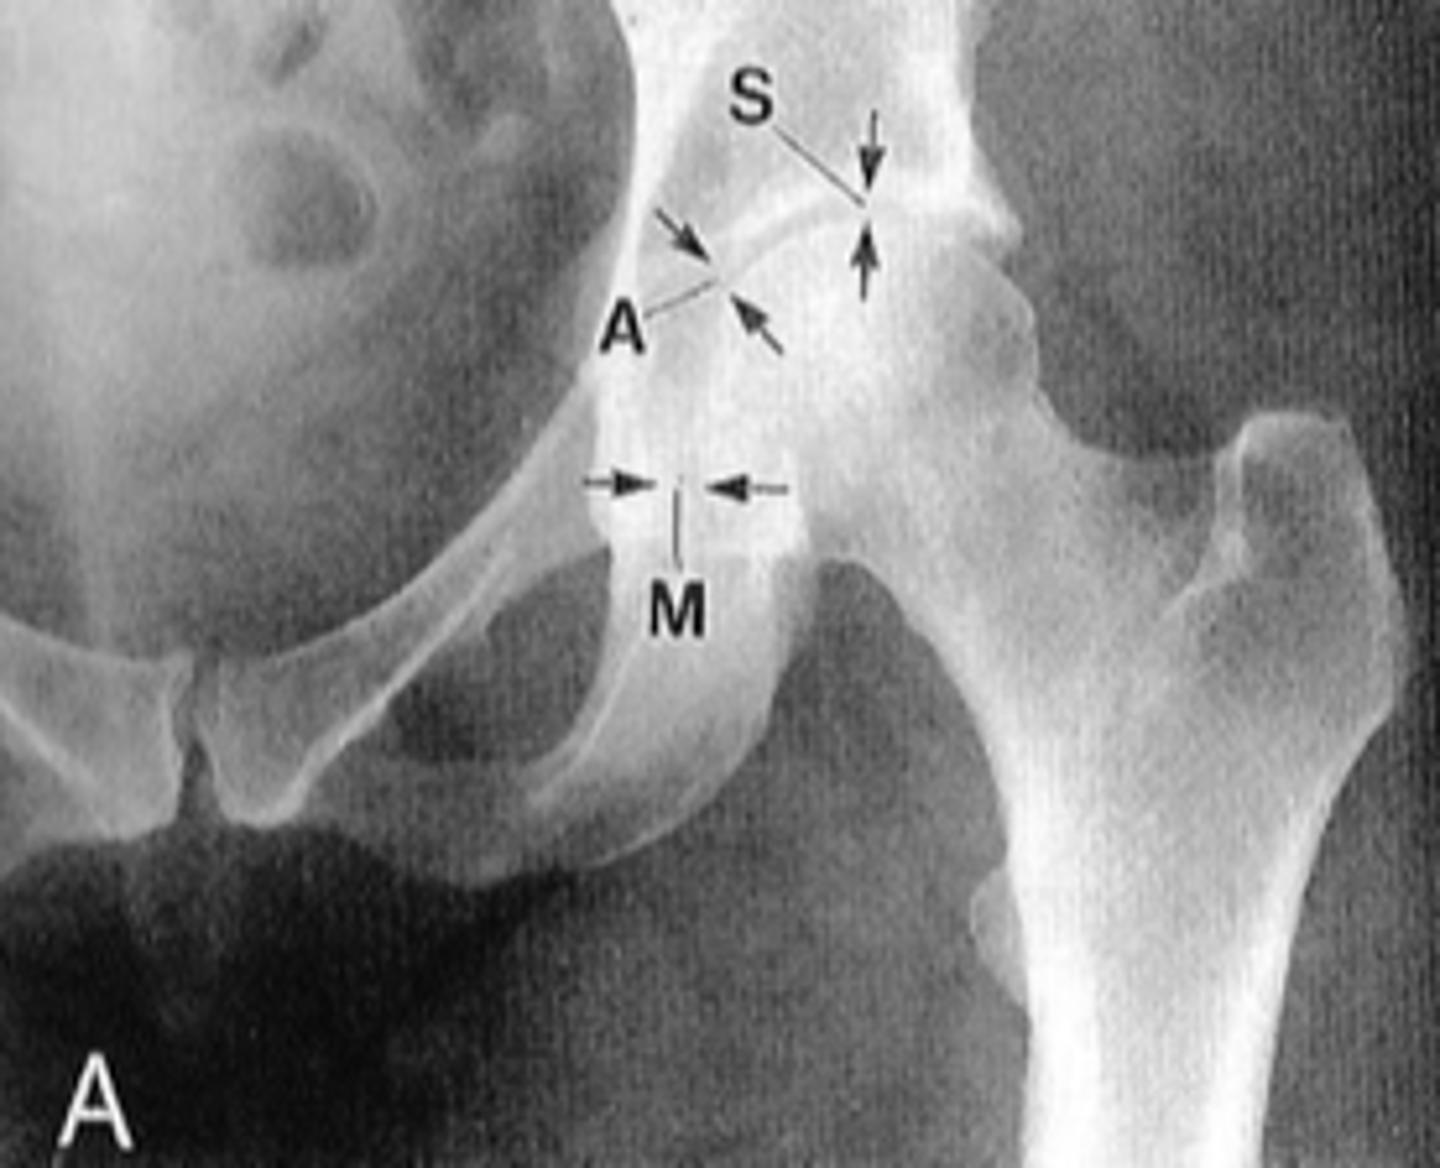

Pubic symphysis

ID 1

<p>ID 1</p>

Left femoroacetabular joint

ID 2 (joint)

<p>ID 2 (joint)</p>

Kohler's teardrop distance

ID measurement line

<p>ID measurement line</p>

- AP pelvis

- AP hip

What views are needed to see Kohler's teardrop distance?

<p>What views are needed to see Kohler's teardrop distance?</p>

- Medial margin of femoral head

- Lateral border of teardrop

Kohler's teardrop distance landmarks

<p>Kohler's teardrop distance landmarks</p>

6-11 mm

Normal Kohler's teardrop distance measurement

<p>Normal Kohler's teardrop distance measurement</p>

2 mm

The normal Kohler's teardrop distance is 6-11 mm, and there should be no greater than a _____ difference when comparing to the contralateral side

<p>The normal Kohler's teardrop distance is 6-11 mm, and there should be no greater than a _____ difference when comparing to the contralateral side</p>

Hip joint effusion

Clinical significance of an enlarged Kohler's teardrop distance

<p>Clinical significance of an enlarged Kohler's teardrop distance</p>

Waldenstrom's sign

What sign indicates an enlarged Kohler's teardrop distance?

- Accentutation of the normal limits

<p>What sign indicates an enlarged Kohler's teardrop distance?</p><p>- Accentutation of the normal limits</p>

Intracapsular swelling/joint effusion

Waldenstrom's sign is usually an indication of _____

<p>Waldenstrom's sign is usually an indication of _____</p>

Inflammatory arthritis

Clinical significance of a small Kohler's teardrop distance

<p>Clinical significance of a small Kohler's teardrop distance</p>

Hip joint space width

ID measurement

<p>ID measurement</p>

Superior, axial, medial joint spaces (SAM)

Hip joint space width landmarks

<p>Hip joint space width landmarks</p>

3-6 mm

Normal superior hip joint space width

<p>Normal superior hip joint space width</p>

3-7 mm

Normal axial hip joint space width

<p>Normal axial hip joint space width</p>

4-13 mm

Normal medial hip joint space width

<p>Normal medial hip joint space width</p>

Joint effusion

Clinical significance of a wide hip joint space

<p>Clinical significance of a wide hip joint space</p>

Arthritis

Clinical significance of a narrow hip joint space

<p>Clinical significance of a narrow hip joint space</p>